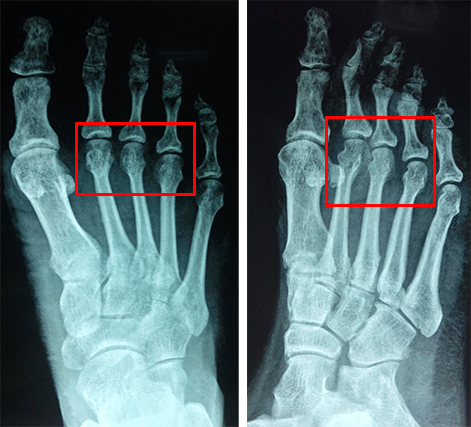

患者男,50岁,体健,跌倒致右足肿痛畸形1小时就诊,查体:右第2-4跖趾关节肿痛畸形,活动受限,末梢血运可,感觉存。X线如下:

诊断:右第二跖骨骨折,右第三四跖趾关节脱位

治疗方案:手法整复。整复后摄X线如下:

伤后三个半月,患者步行自如复诊,复查X线如下(原右第二跖骨骨折断端对位对线良好,原右第三四跖趾关节脱位已复位):